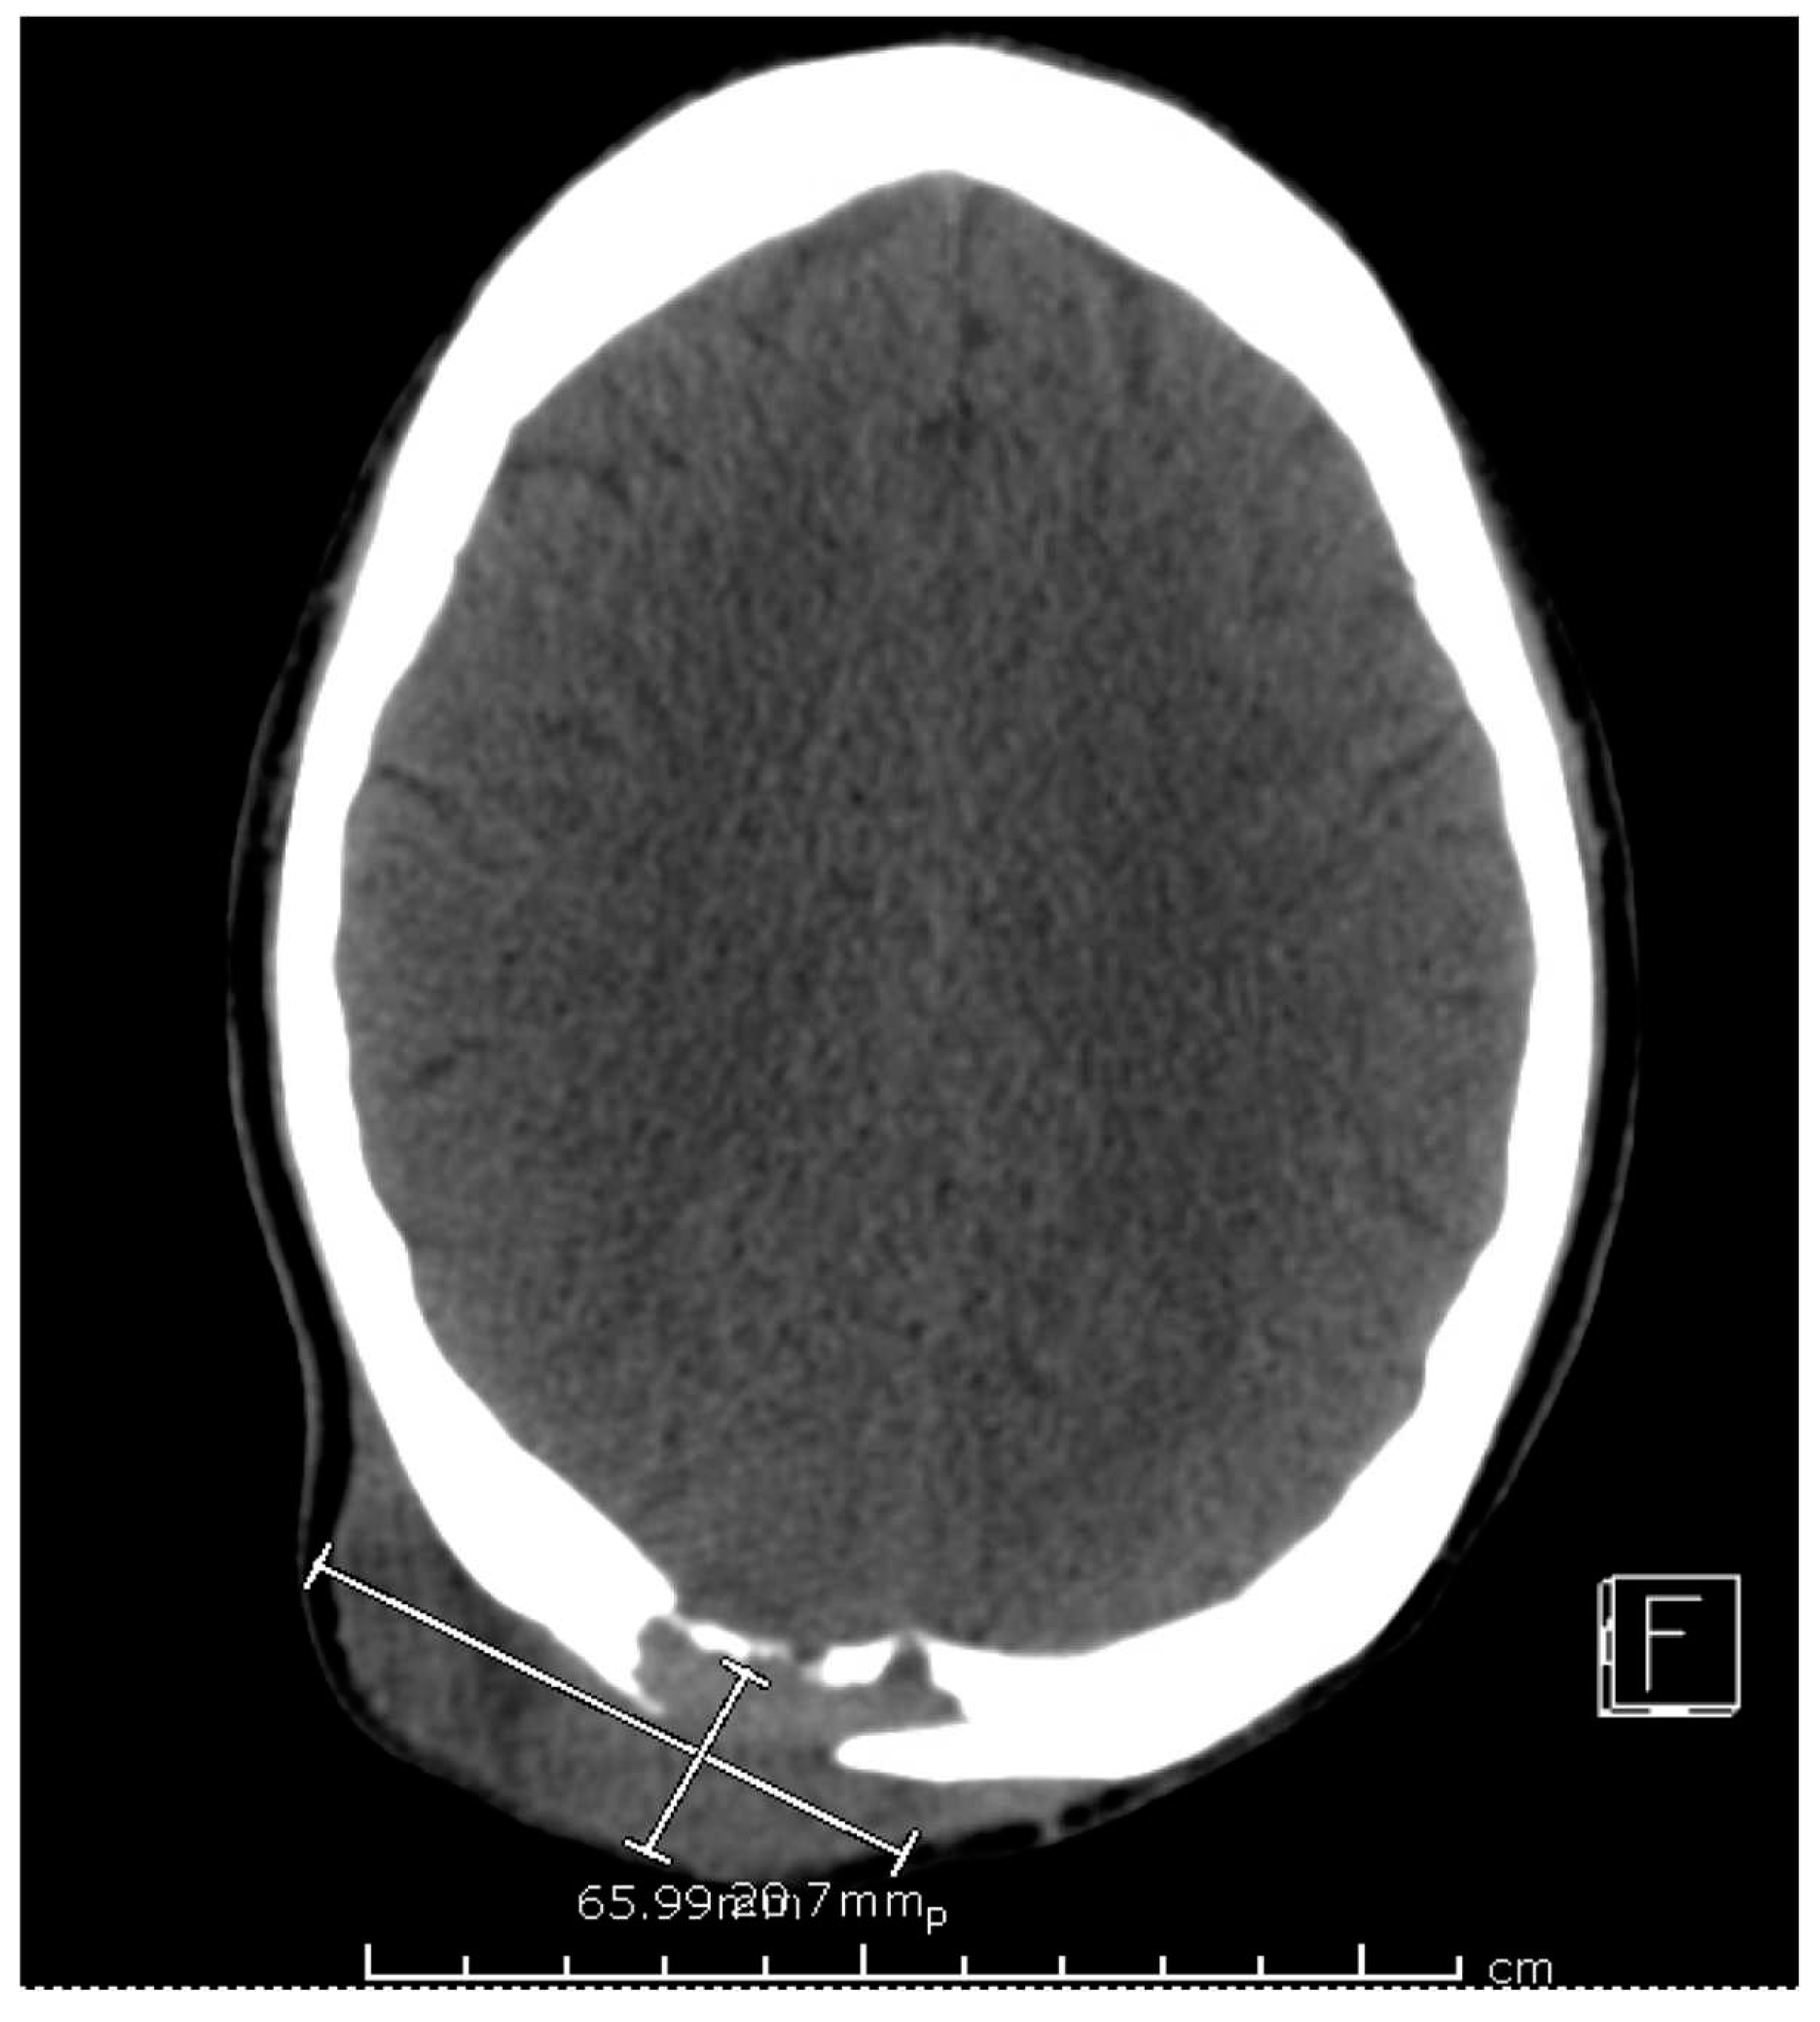

Computed tomography (CT) scan of his chest and abdomen revealed a right upper lobe cavitary lesion abutting the ribs and a sinus tract from his left ischium to the skin over his left lower abdomen (Figure 2). Additionally, a magnetic resonance image (MRI) of his head was obtained which demonstrated a mass extending from his right occipital skull with evidence of skull erosion as well (Figure 3).

Figure 3. MRI Brain.